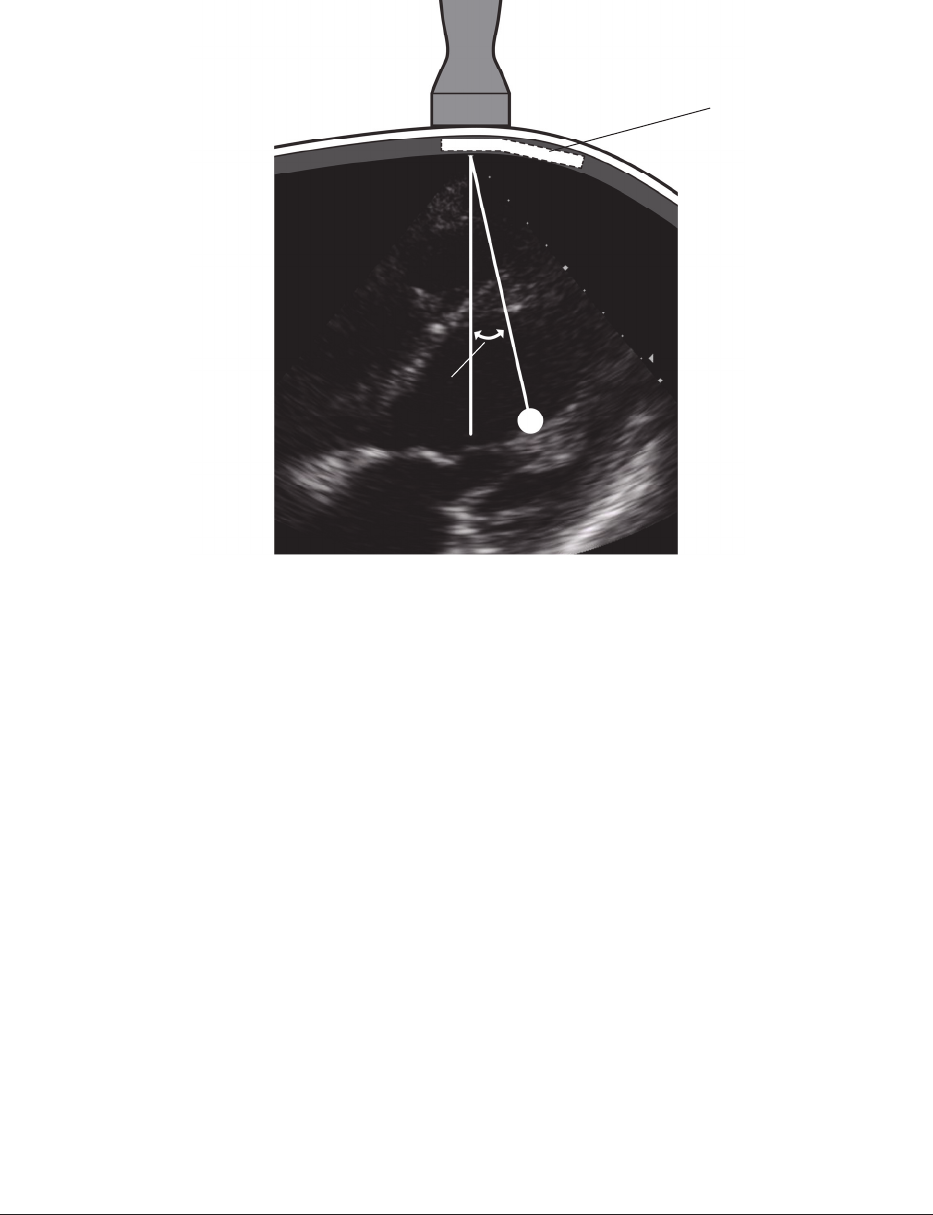

Figure6: Withultrasoundassistance,markwherethe5thICSopensto1cm

Theultrasoundimagedisplaysthecostalcartilages(annotatedCC)andthe5thICSwhichcanbe

usedtodeterminethelocationwherethespacingbetweenthecostalcartilagesopensto1cm.